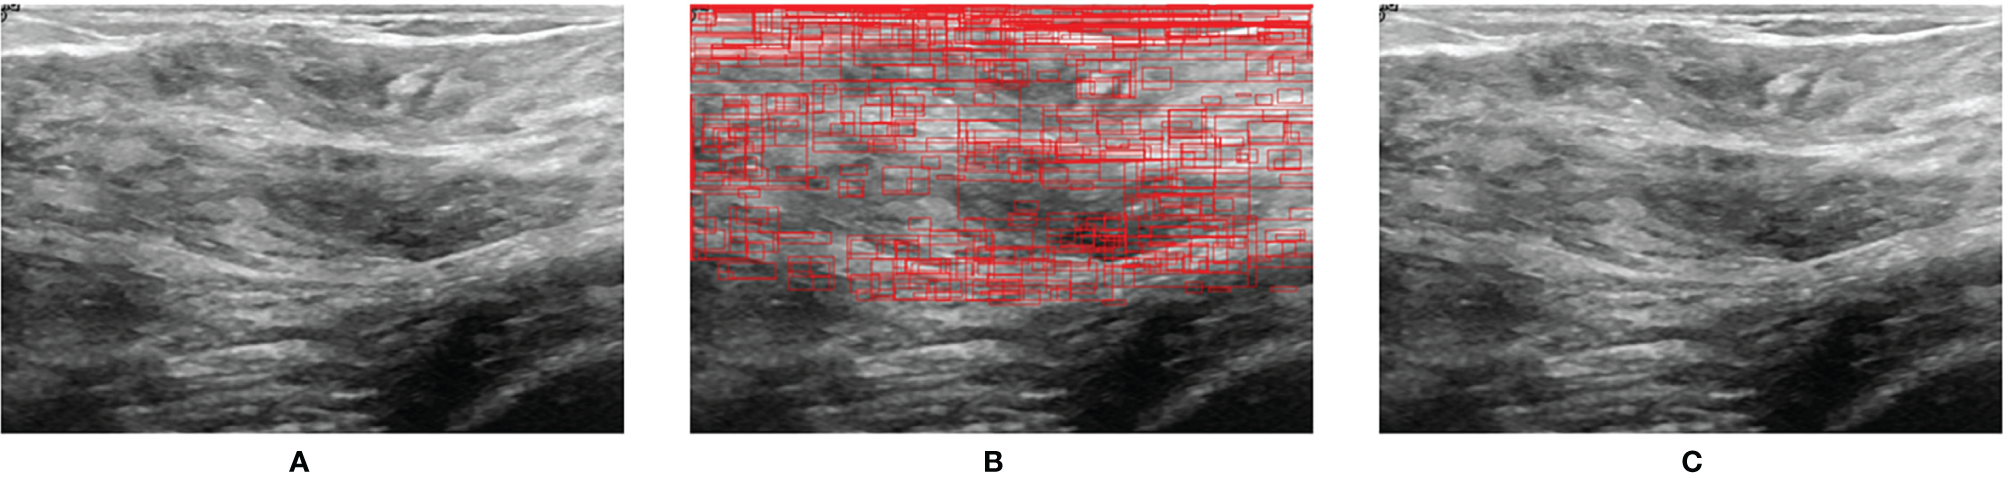

Figure 7 shows the prediction result when a normal US image is inputted into BUSnet. No lesion box is identified in the output.

Figure 7

Prediction for a normal US image. (A) Original image. (B) RoIs obtained after selective search. (C) Final output.